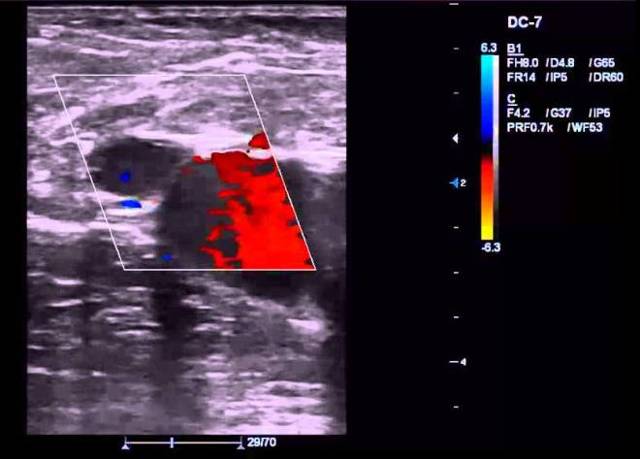

Дуплексное ангиосканирование, или УЗДС, отличается от первого наличием возможностей цветного картирования, позволяющего дополнительно определять направленность тока крови. Потоки, следующие в разных направлениях, приобретают различные цвета, что является для специалиста неоценимой информацией, дающей возможность комплексно определять показатели состояния сосудов.

Этот вариант УЗИ имеет две составляющие – классическая допплерометрия и в дуплексном режиме с цветовым картированием. Кроме определения структуры сосуда, скорости кровотока, УЗДС вен нижних конечностей позволяет определить направление потоков крови, которые под действием ультразвука получают разное цветовое окрашивание.

Нормальный кровяной поток направляется из поверхностных вен в глубокие. Во время триплексного сканирования (триплекса) с цветным картированием кровоток окрашен в синий цвет.

Если имеется варикоз, нарушается работа венозных клапанов, что способствует обратному току крови. Как следствие, кровоток на мониторе будет красного цвета.